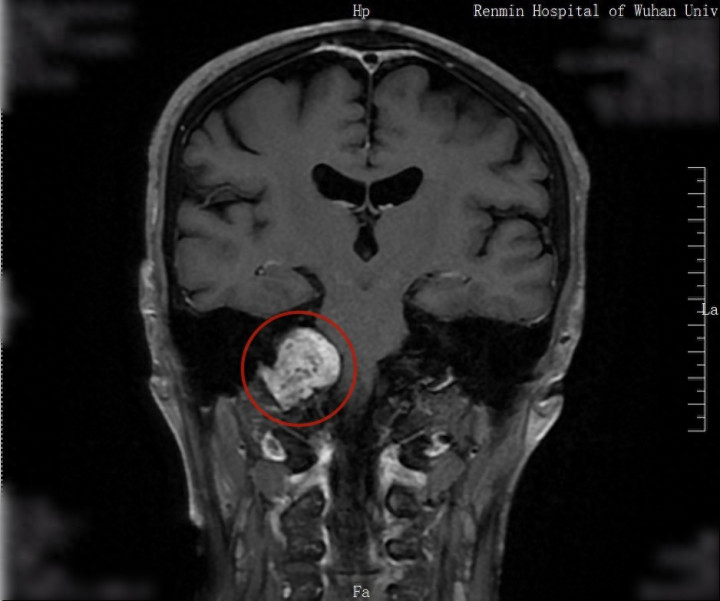

一颗直径6公分、压迫脑干的颈静脉孔区神经鞘瘤,居然在又名60岁男人的颅内暗暗“冬眠”了10余年,直到近期男人因精神阻止剧烈发作就诊时,这颗不仅影响形态、同期危及人命的“隐形炸弹”才被偶然揪出。

住院CT查验中,大夫偶然发现后来颅窝内藏有一个直径约6公分的庞杂肿瘤,已严重挤压脑干。进一步核磁共振及脑血管造影查验透露,该肿瘤发祥于颈静脉孔区,向颅外及颈部孕育。

该院精神科、神经外科、耳鼻咽喉头颈外科、麻醉科等多学科众人诊断后暗意,该肿瘤虽为良性但孕育位置稀奇——颈静脉孔区由枕骨、颞骨岩部等多种骨性结构围成,周围密布三叉神经、面听神经、迷跑神经等多组颅神经,以及小脑上动脉、小脑前下动脉等迫切血管。该处肿瘤对东谈主体各器官功能影响极大,若不足时休养将危及人命,手术切除是最好有策画,同期手术风险极高。